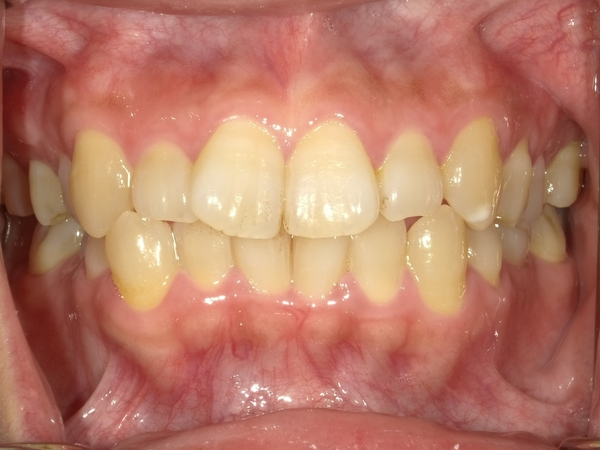

◯ご相談内容:歯並びが気になる◯矯正の種類:マウスピース型矯正「インビザラインGO」◯治療期間:20週間◯治療費用:44万円(税込)